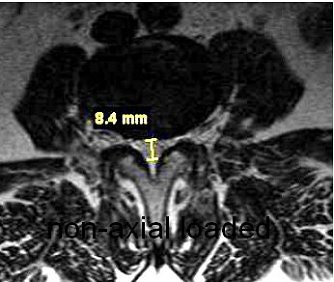

| Nonaxial loaded (above), transaxial T1-weighted images showed increased stenosis by 3.2 mm of the central spinal canal at the L3-L4 level with axial loading (below). |

Willen and Danielson have also shown that axial-loaded imaging, during recumbent MRI or CT, simulates weight-bearing forces in the lumbar spine, provoking narrowing of the central spinal canal and neural foramina, and increasing the diagnostic accuracy of dynamic spinal stenosis. Dynamic stenosis has been defined in literature as a change in the cross-sectional dural sac area of greater than 15 mm² resulting in a decrease in the dural sac area to less than 75 mm (Spine, December 1, 2001, Vol. 26:23, pp. 2607-2614; Acta Radiologica, November 1998, Vol. 39, 6, pp. 604-611; Spine, December 1, 2001, Vol. 26:23, pp. 2601-2606).

Axial loading may show functional spinal changes in apparently normal segments. Dr. Shinji Kimura, Ph.D, and colleagues found that the axial force of 50% body weight in supine posture simulates the upright lumbar spine morphologically, significantly decreasing the disk height at L4-L5 during compression (Spine, December 1, 2001, Vol. 26:23, pp. 2596-2600).